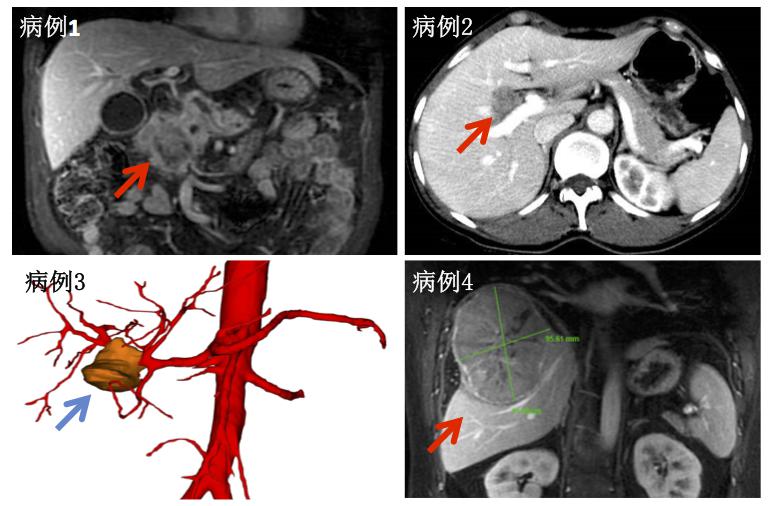

图为四位肝胆胰疾病患者术前影像学资料(病例1:胰头癌侵犯肠系膜上静脉磁共振图像;病例2:右肝管占位增强CT图像;病例3:胆囊癌侵犯肝门部患者三维重建动脉图像;病例4:巨大肝癌Ib期伴破裂出血患者增强磁共振图像)

病例一为男性,65岁,因眼黄尿黄五天入院,进一步检查发现胰头部肿瘤大小达5.2cm,并侵犯肠系膜上静脉及门静脉长达5cm,紧邻肠系膜上动脉,手术切除率低,手术风险大,但在手术团队努力下为患者成功完成根治性胰头肿瘤切除并完整切除受累血管,在切除受累血管的同时完成人工血管替代及消化道重建,代表胰腺外科国内一流手术水平;病例二为52岁女性,右肝管占位合并胆囊胆总管结石术中证实为右肝管绒毛状腺瘤局部高级别上皮内瘤变,行胆囊切除胆总管切开电子胆道镜探查取石+右肝管肿瘤切除及右肝管空肠吻合术,术中行精准确定性手术体现胆道疾病系统性治疗的极高水平;病例三为56岁女性眼黄尿黄入院,术前行PTCD减黄半月,考虑为胆囊体部癌侵犯左右肝管汇合部及右肝动脉,肿瘤分期晚考虑T4N0M0,IVA,手术难度大,但术中完整切除肿瘤顺利完成胆囊癌根治术,体现胆道系统肿瘤诊治最高水平;病例四为37岁年轻男性,乙肝肝硬化合并巨大肝癌破裂伴网膜包裹,术中为患者行巨大肝癌及周围包裹网膜切除腹腔清洗术,体现复杂肝癌诊治超高水平。